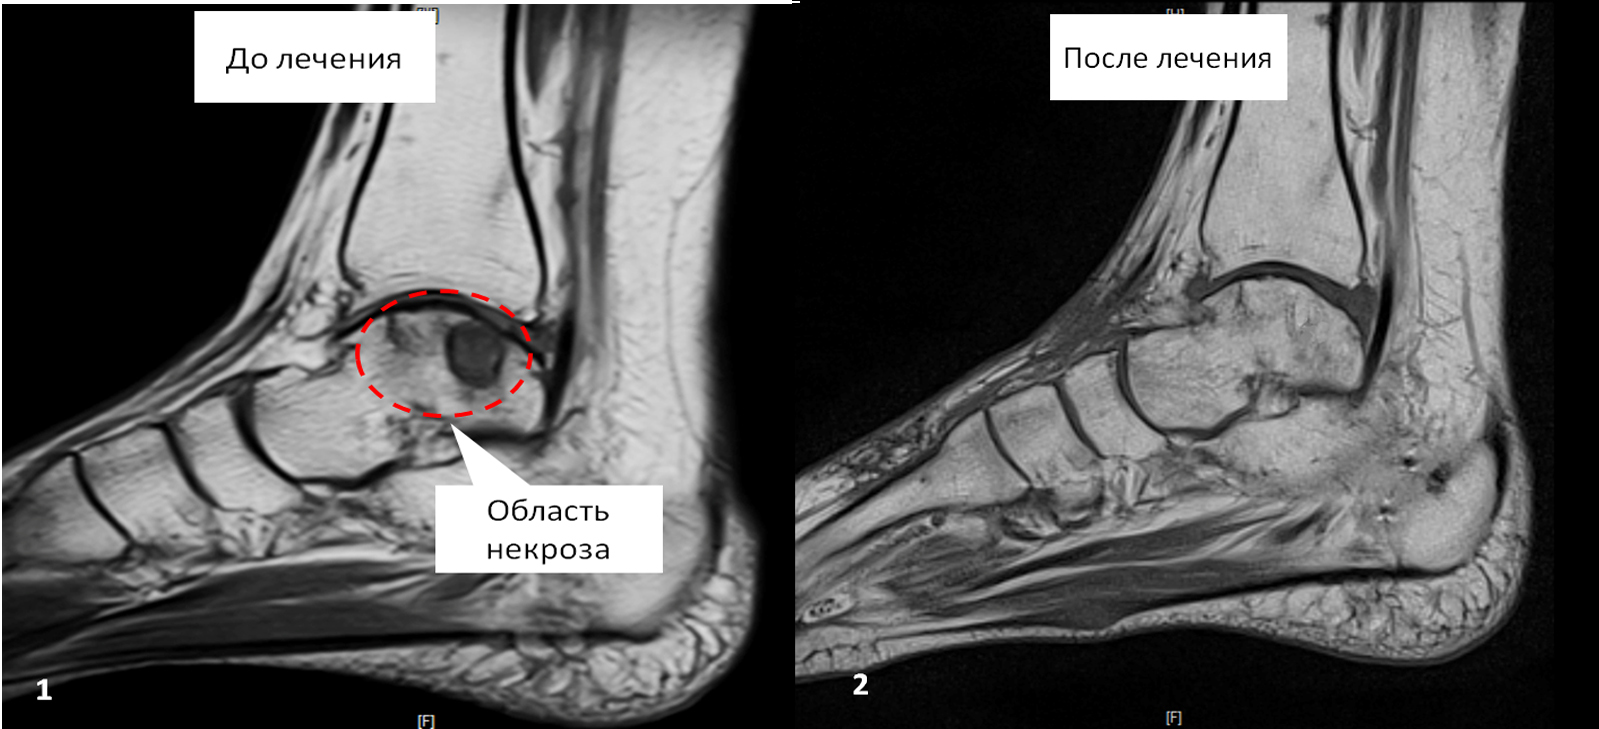

У девушки был диагностирован аваскулярный некроз таранной кости. Консультировалась в различных медучреждениях, в том числе и Германии. Предлагали выполнить операцию по удалению мертвого участка кости и артродезирование (замыкание) голеностопного сустава, после которой никаких движений в суставе не было бы.

Мы осуществили восстановительное оперативное лечение с использованием клеточных технологий (стволовых клеток).

Через шесть месяцев после операции костная структура таранной кости полностью восстановилась. Беспокоившие ранее боли в суставе полностью ушли, движения в голеностопном суставе восстановились в полном объеме.